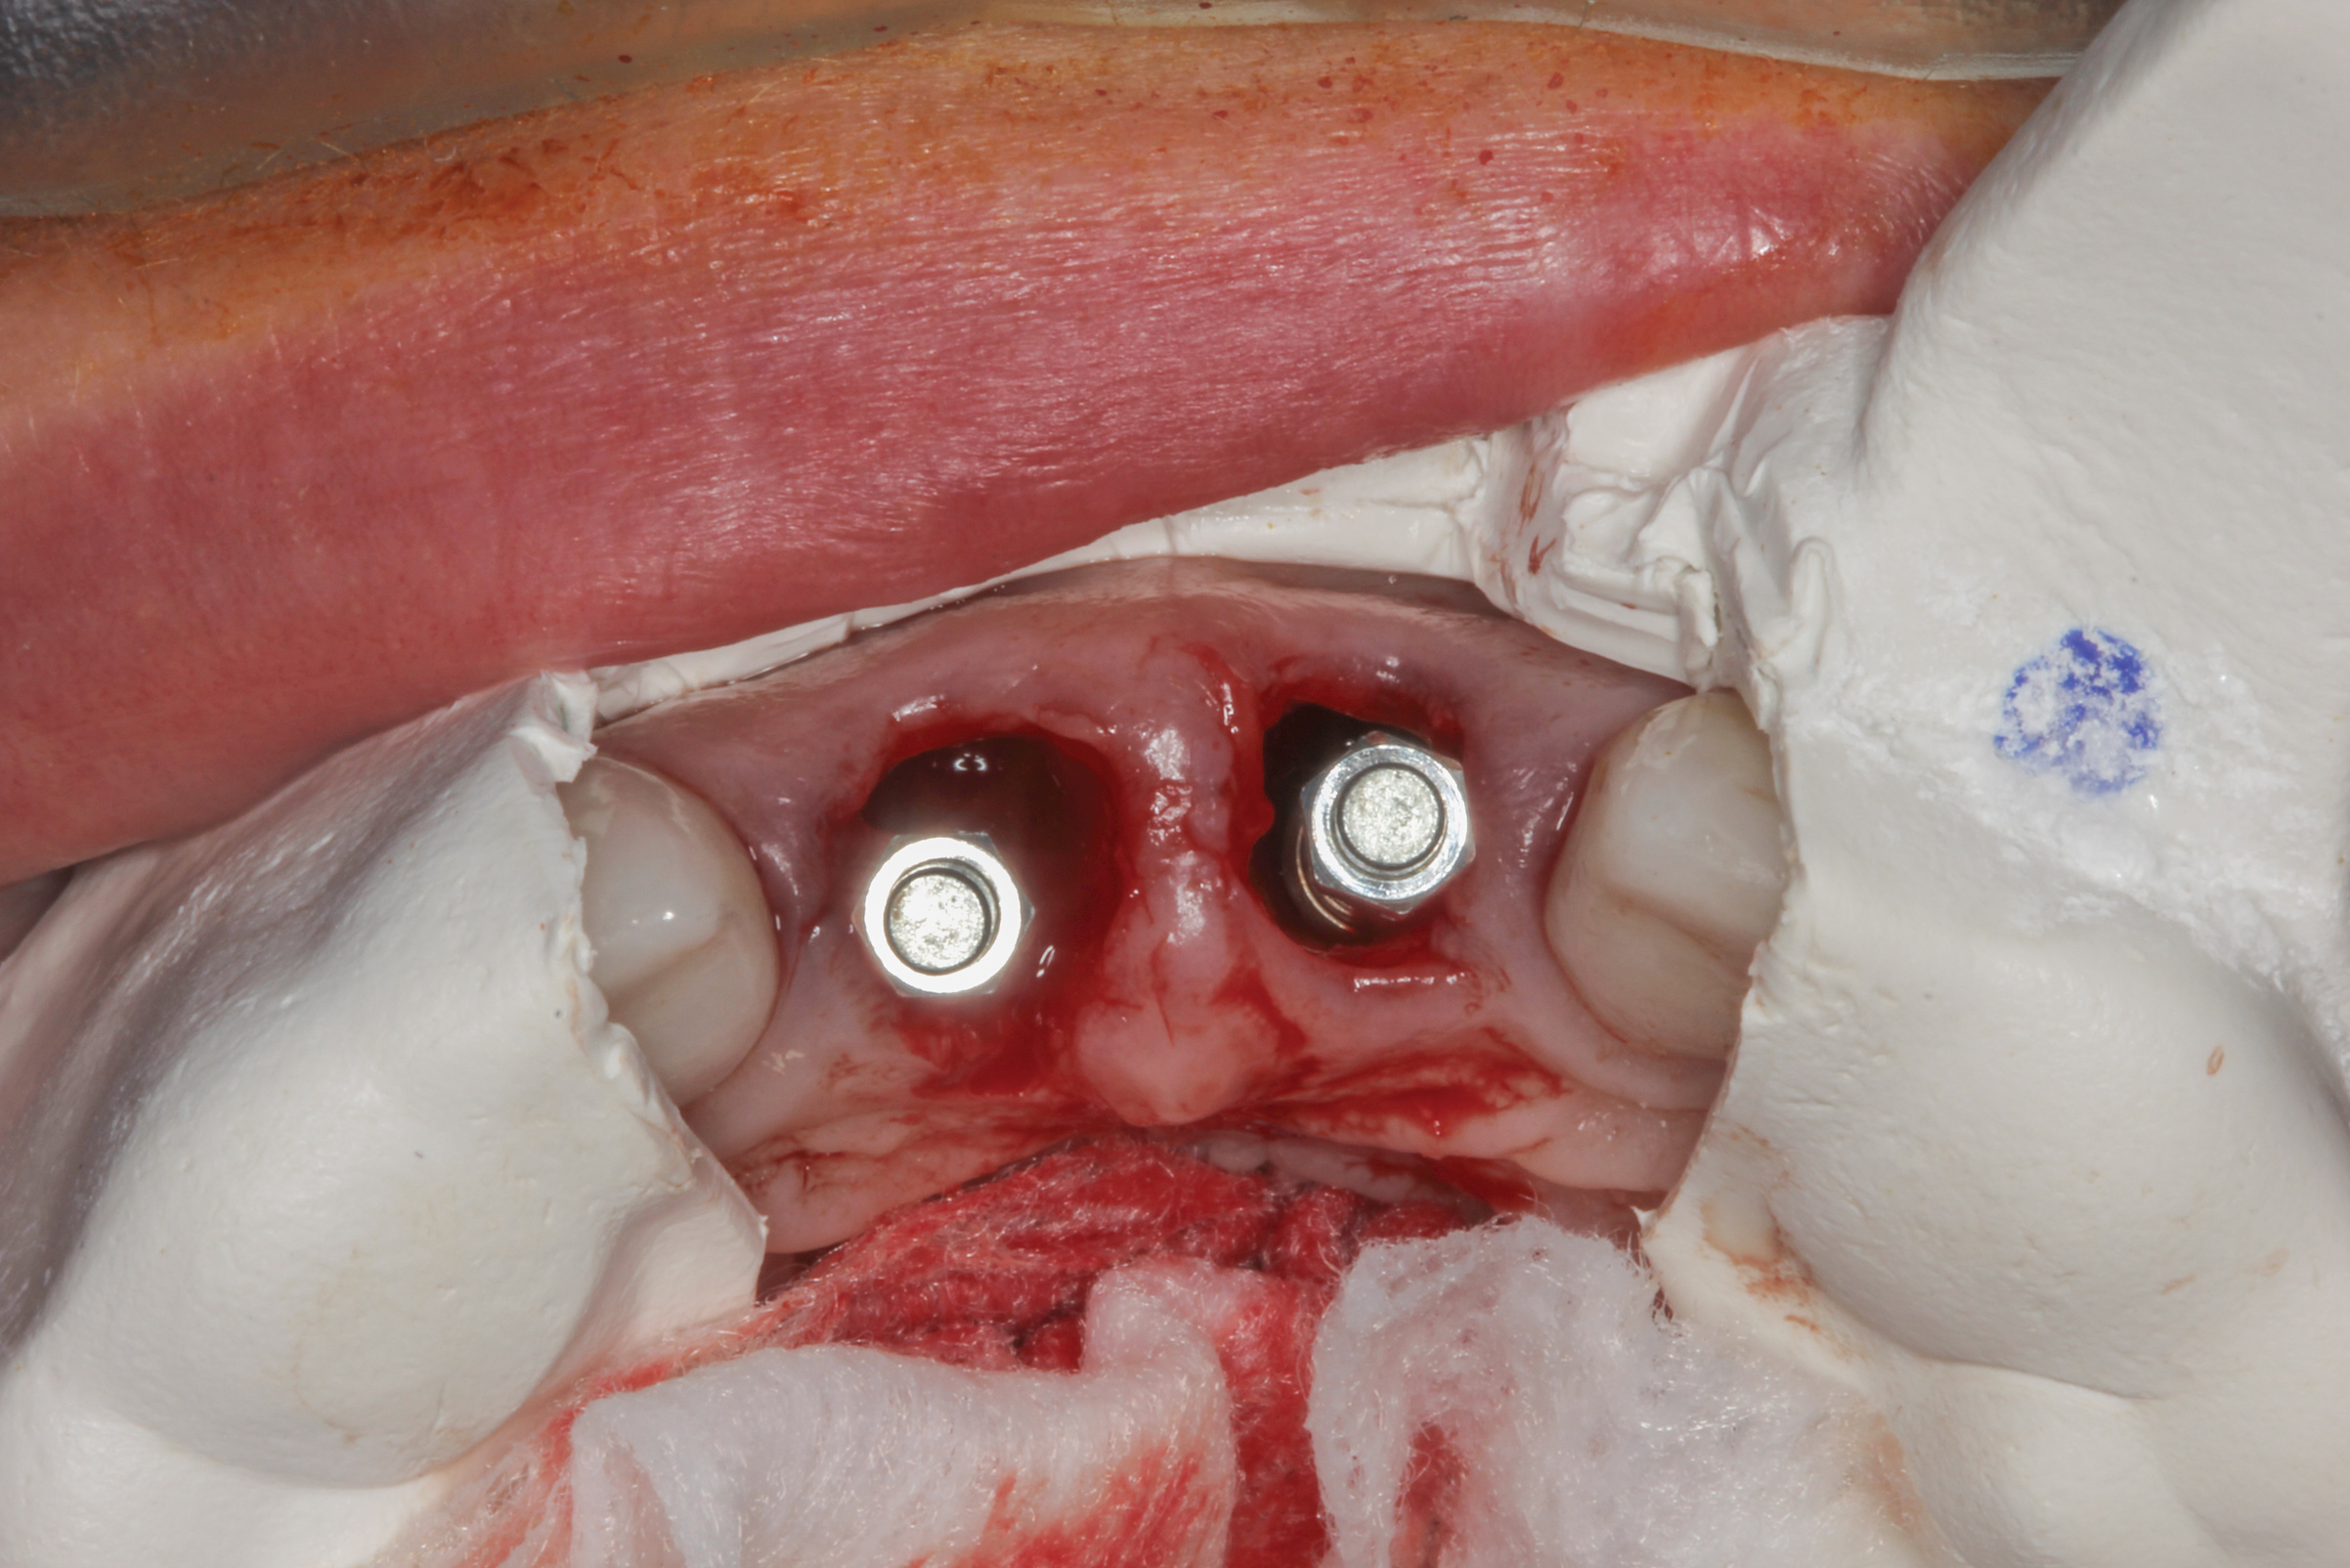

The surgery was performed under local-regional anesthesia. The thermoplastic retainer was placed over the remaining teeth and its fit/stability verified. Atraumatic extractions of teeth Nos. 8 and 9 were performed, and intact buccal bone was verified. Osteotomy site preparation and immediate implant placement were performed using the dynamic surgical navigation system. Two 3.6 mm x 9 mm implant fixtures (Astra Tech EV, Dentsply Sirona, dentsplysirona.com) were placed. SmartPegs (Osstell, osstell.com) were attached to the implants to show the trajectory of the fixture positioning. After implant placement, anorganic bovine bone matrix (Bio-Oss®, Geistlich Pharma, geistlich-na.com) was used to graft the implant alveolus "gap," and healing abutments were placed (Figure 9 and Figure 10). The patient was provided with an interim removable appliance for tooth replacement.

Fig 9. Dynamic surgical navigation, demonstrating flapless immediate implant placement. “Smart pegs” were placed to show the trajectory of the fixture positioning.

Figure 9